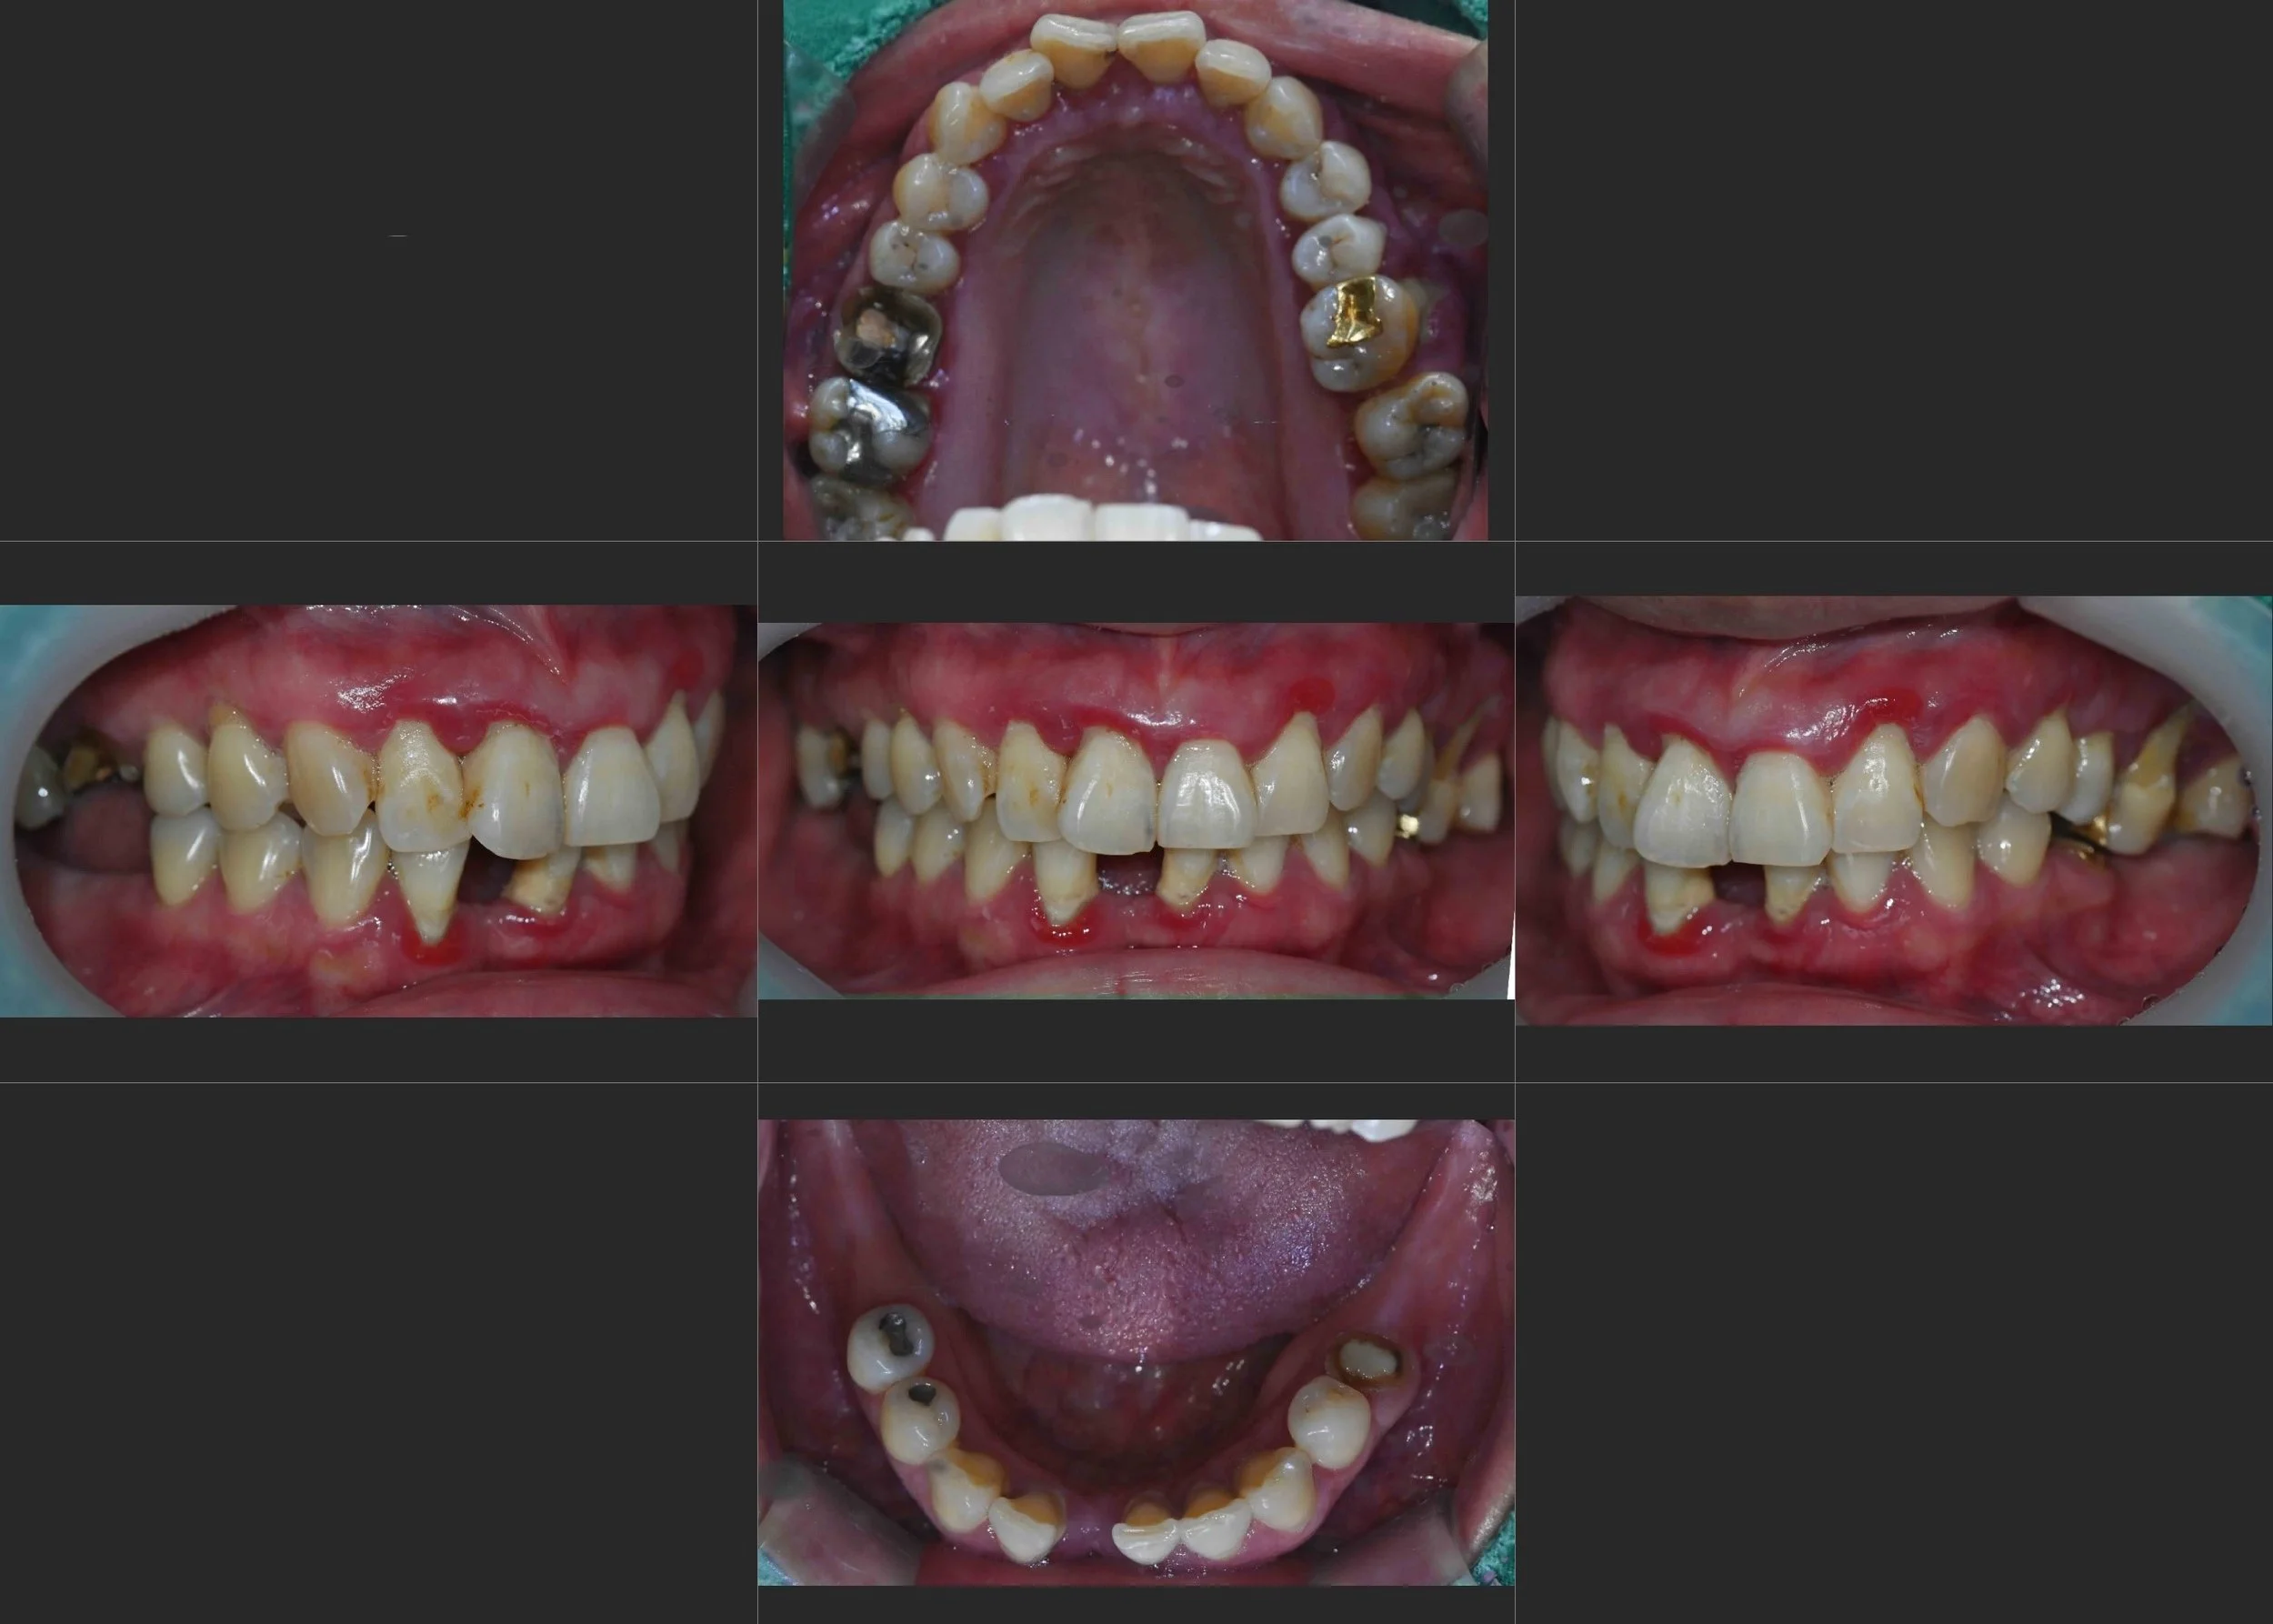

OPG - BEFORE

INTRA ORAL - BEFORE

The patient presented with moderate to advanced periodontitis, posterior occlusal loss,

and partial anterior tooth loss accompanied by mobility of the remaining teeth.

Due to prolonged edentulism in the anterior region, the patient had largely abandoned

esthetic expectations and adapted to a compromised functional state.